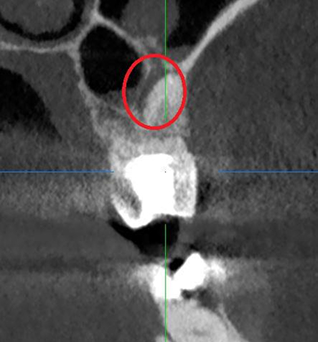

Перелечивание зуба с кистой под микроскопом

Проблема: У пациента отек щеки, боли самопроизвольные, усиливающиеся при приеме пищи, неудачное первичное лечение зуба (старыми методами).

Лечение: Проведено эндодонтическое перелечивание зуба под дентальным микроскопом, что позволило точно выявить анатомические особенности корневых каналов и устранить последствия ранее некачественного лечения. После купирования воспалительного процесса (киста) каналы герметично запломбированы. Коронковая часть зуба восстановлена для сохранения функции и герметичности до этапа постоянного протезирования.

Результат: После проведённого лечения болевые ощущения полностью устранены, отёк щеки исчез, воспалительный процесс купирован. Зуб сохранён, восстановлена его функция. Установлена коронка, что позволило полностью восстановить анатомическую форму и жевательную эффективность зуба.